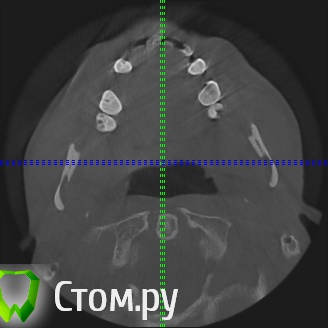

sergey765 Опубликовано 11 июня, 2014 Автор Поделиться Опубликовано 11 июня, 2014 посмотрите пожалуйста КТ. Ссылка на комментарий

sergey765 Опубликовано 11 июня, 2014 Автор Поделиться Опубликовано 11 июня, 2014 могу вам ещё снимков выложить.их довига. беспокаят меня боли после удаления .прошло 5 недель. снимки девушка лет 20 эти смотрела. сказала что у меня там инфекции дофига. типа давай я тебя на понедельник к хирургу запишу. он ранку вскроет. прочистит Ссылка на комментарий

Bier Опубликовано 11 июня, 2014 Поделиться Опубликовано 11 июня, 2014 это все не информативные кадры, в прикрепленных темах есть инструкция, выкладывайте КТ целиком, наш рентгенолог скачает и выложит срезы. 3 Ссылка на комментарий